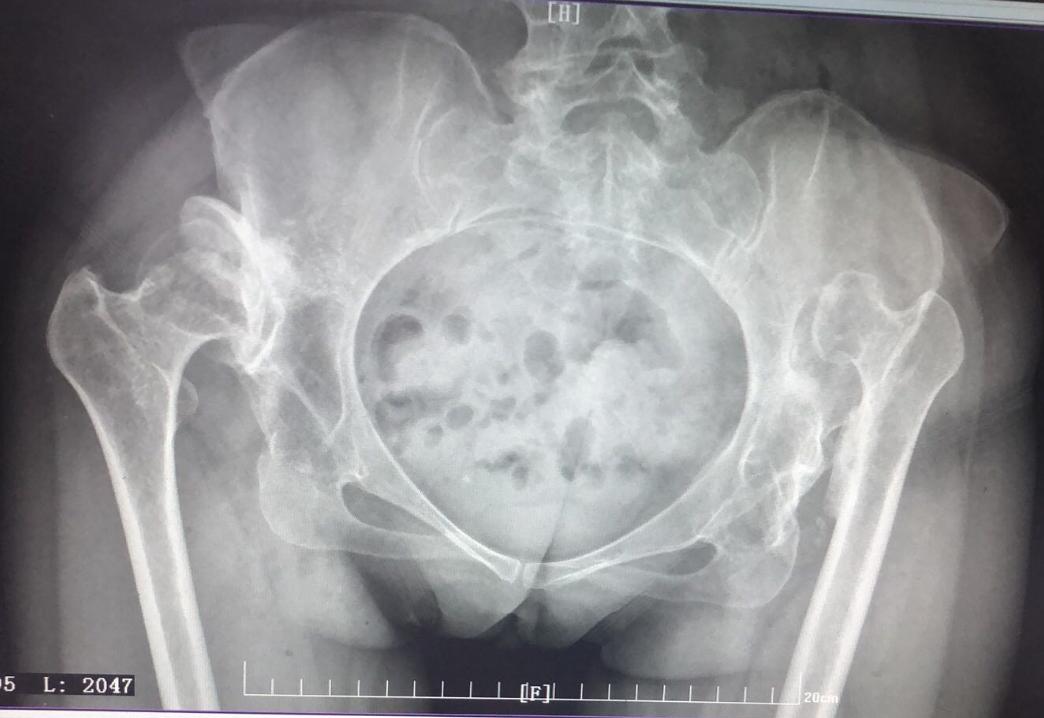

在正位X线片上,髋白发育不良主要表现为髋白发育浅小或浅平,股骨头的负重侧间隙增宽,并继发骨性关节炎。髋关节正位、蛙位X线片是了解与判断髋关节发育不良程度的最基础的影像学检查。

髋关节CT检查有利于分析髋臼形态、判断髋臼缺损及增生情况,可为术式选择、评估假体型号和安装位置等提供帮助。MRI检查有助于发现关节盂唇损伤、关节囊改变及骨内信号改变等。